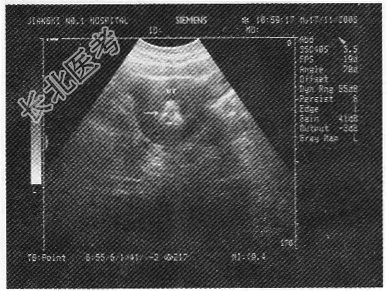

- 单项选择题中年女性,超声下腹横切面如图, 箭头所示为

A、子宫钙化环

B、宫内节育器

C、子宫肌瘤

D、妊娠囊

E、钙化的子宫肌瘤

- 中年女性,超声下腹横切面如图, 箭头所示